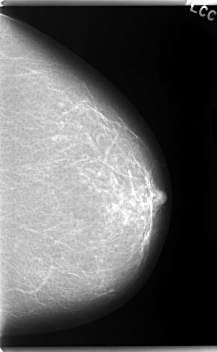

C_0057_1.RIGHT_CC

C_0057_1.LEFT_CC

LEFT_CC LINES 5976 PIXELS_PER_LINE 3680 BITS_PER_PIXEL 12 RESOLUTION 50 NON_OVERLAY